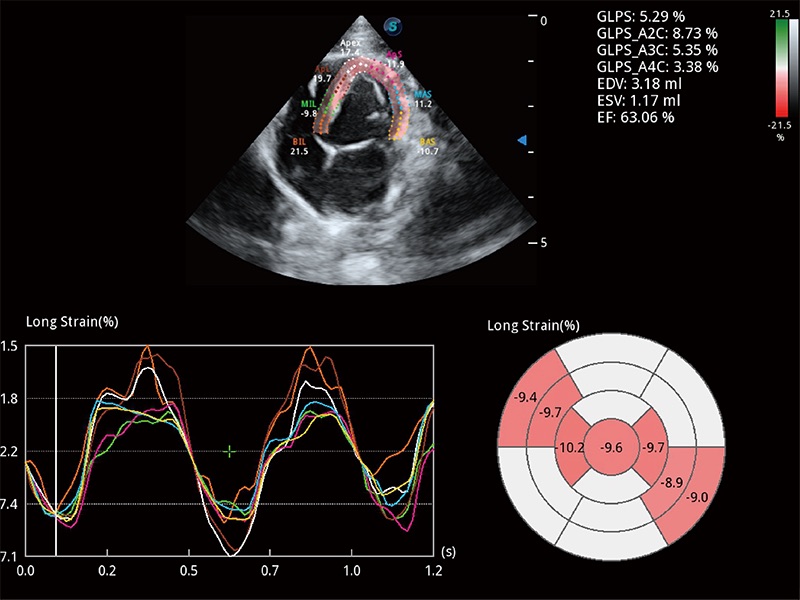

实时用颜色表示心肌组织运动,观察和定量组织的运动情況,对快速检测与评估心肌的灌注和活性、电传导及心肌收缩和舒张功能等均能提供重要的诊断信息。

通过心肌识别技术与二维斑点追踪技术相结合,对心脏的超声图像进行量化分析。计算心肌17个节段的应变、应变率、速度、位移等,并通过牛眼图的形式进行呈现。

具备多种协议可选,同时支持17阶段划分法和专业的SE报告。

能够基于左心室壁追踪和辛普森法,自动计算射血分数,支持多个可移动点描迹,与手动测量相比,极大节省了动物医生的时间和精力。